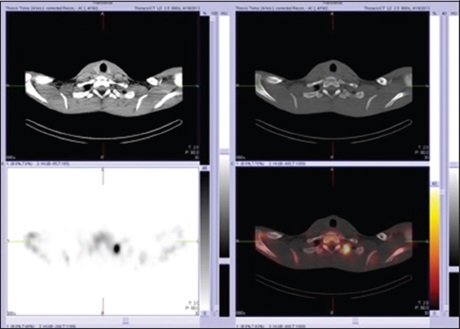

Hybrid single‑photon emission computed tomography‑computed tomography: A review of literature

Dr. Garba Haruna Yunusa, Abubakar Farate, Abubakar K Lawal, Zabah Muhammad Jawa (Author)

121-127